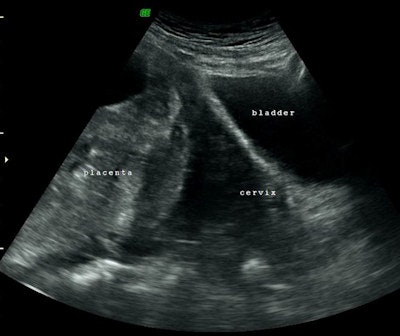

Over the last two years, 12 women (ages 28-46) who urgently needed uterine arteries ballooning and embolization to prevent and control bleeding after a C-section were referred to the interventional radiology service at Al Ain Hospital. Seven of these women were diagnosed with invasive placenta that was confirmed by a predelivery MRI. Interventional radiologists worked in a multidisciplinary team with obstetricians. The interventional radiologists guided balloon catheters into a woman's left and right uterine artery (preoperative prophylactic insertion of bilateral internal iliac artery occlusion balloons) before delivery -- to be ready to inflate (just like in angioplasty), if needed at delivery to block excessive blood flow.

Often these women are scared; this is a very serious and dangerous condition. Before interventional radiology treatment was available, the placenta couldn't be delivered and women would need a hysterectomy, or in some cases died. At our hospital, interventional radiologists control excessive bleeding in women with a combination of balloon catheters inserted into uterine arteries predelivery (that could be inflated to control bleeding, if necessary), and uterine artery embolization after delivery (if the placenta could not be delivered).